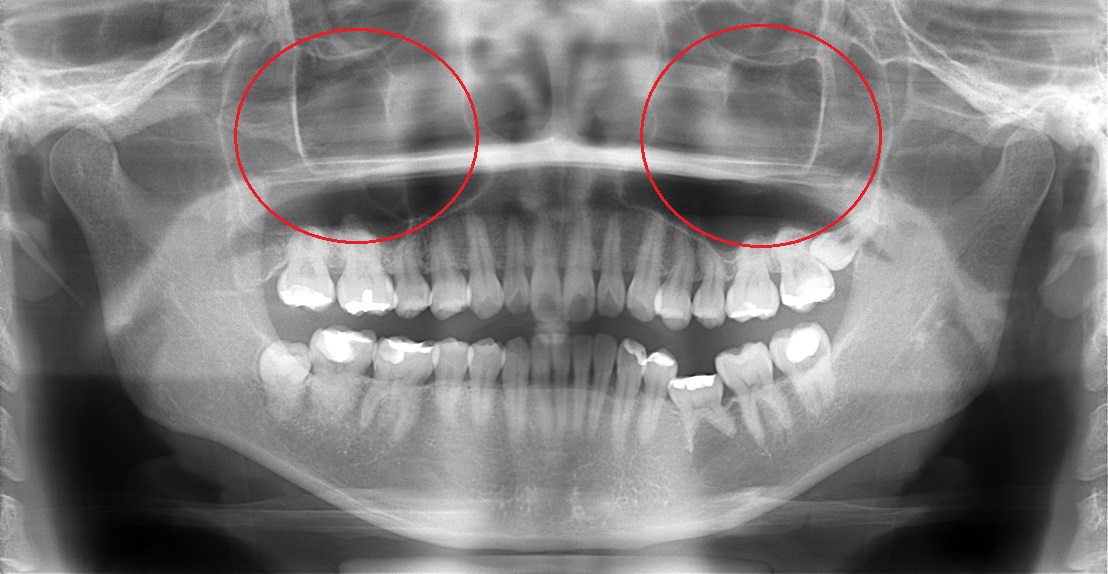

| 歯性上顎洞炎 (Odontgenic Sinusitis) |

上顎のう蝕(むし歯)や歯周病をひき起こした細菌による炎症が上顎洞に波及することがあります。

これを歯性上顎洞炎(歯が原因の蓄膿症)と呼びます。

上顎洞は上顎の歯根と接近しているため、う蝕や歯周病を治療しないで放置していると、歯性上顎洞炎になることがあります。

鼻性は両側にみられますが、歯性は片側だけに起ることが多いようです。